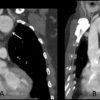

Phình ĐM chủ

» Thông tin: Nam giới – 45 tuổi.

» Lâm sàng: Đau ngực.